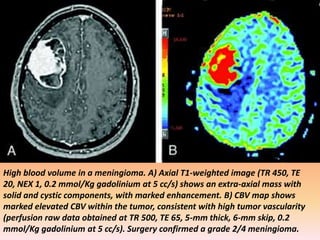

High blood volume in a meningioma. A) Axial T1-weighted image (TR 450, TE

20, NEX 1, 0.2 mmol/Kg gadolinium at 5 cc/s) shows an extra-axial mass with

solid and cystic components, with marked enhancement. B) CBV map shows

marked elevated CBV within the tumor, consistent with high tumor vascularity

(perfusion raw data obtained at TR 500, TE 65, 5-mm thick, 6-mm skip, 0.2

mmol/Kg gadolinium at 5 cc/s). Surgery confirmed a grade 2/4 meningioma.